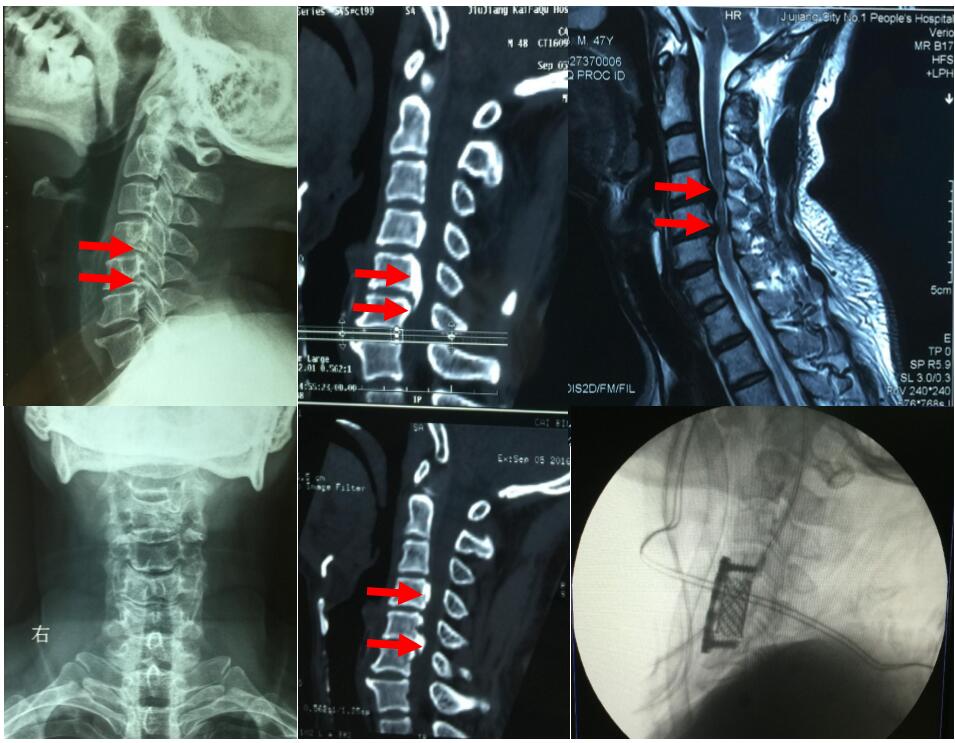

如果患者骨质增生较为严重,出现压迫神经的现象,可能会导致患者发生颈背疼痛、四肢无力、手指发麻、行走困难 背疼痛、四肢无力、手指发麻、 以及头晕恶心的症状;如果患者的椎动脉受到了压迫,那么患者的睡眠质量就会下降,导致患者的心情和精神都受到了影响,所以颈椎骨质增生的危害很大;如果增生组织对于神经根的压迫非常严重甚至可能导致患者发生瘫痪的严重后果。

通过以上介绍可以看出颈椎骨质增生对于患者的健康有着较为严重的威胁。一旦发生了常见的颈椎骨质增生的症状务必积极的去医院检查治疗。对于一些骨质增生并不是非常严重的患者,建议使用中医方法治疗;对于一些非常严重、病史较长的颈椎骨质增生患者建议采取手术治疗的方法。治疗的过程中还应该根据自己的情况制定科学有效的颈椎护理工作,日常养成良好的工作、生活习惯,如此多多管齐下,才能更好地治疗颈椎骨质增生,避免严重的疾病危害发生。